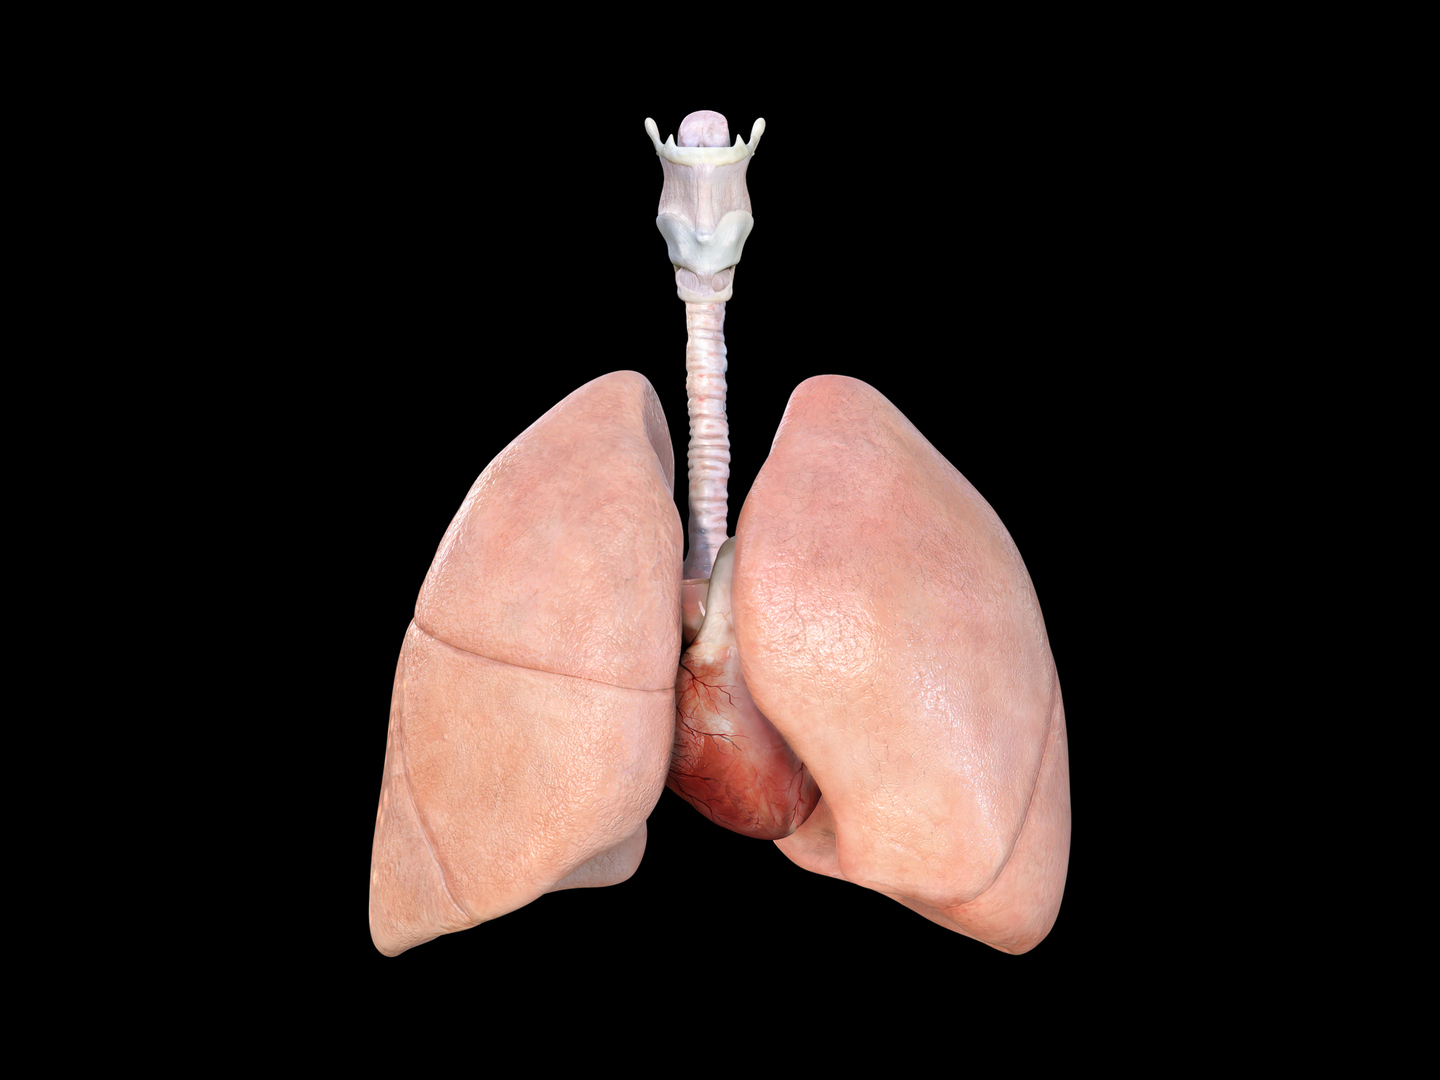

علماء يبتكرون رئة بشرية مصغرة تحاكي اﻷمراض وتختبر الأدوية بدقة

نجح فريق من العلماء في تحقيق إنجاز طبي كبير تمثل في تطوير نموذج مصغر للرئة البشرية باستخدام خلايا جذعية من شخص واحد فقط.

وهذا النموذج الدقيق ليس مجرد تقنية معملية متطورة، بل هو بوابة تفتح آفاقا جديدة لفهم الأمراض التنفسية وعلاجها بطريقة مخصصة لكل مريض على حدة.

ويعتمد هذا الابتكار على مبدأ بسيط عميق: إذا استطعنا إنشاء نسخة مصغرة من رئة شخص ما في المختبر، فسنتمكن من دراسة كيفية استجابتها للأمراض المختلفة واختبار فعالية الأدوية عليها قبل تقديمها للمريض نفسه.

وتمكن الفريق البحثي من تحويل الخلايا الجذعية المأخوذة من متبرع واحد إلى جميع أنواع الخلايا الرئوية الأساسية، ما جعل النموذج الجديد يتميز بأن جميع مكوناته البيولوجية متطابقة وراثيا ومشتقة من مصدر واحد.

ويقول الدكتور ماكس غوتيريز، الباحث الرئيسي، إن هذه التقنية تتيح لأول مرة دراسة الأمراض التنفسية بطريقة شخصية لم تكن ممكنة من قبل. فبدلً من الاعتماد على نماذج عامة أو تجارب على حيوانات تختلف بيولوجيا عن البشر، أصبح بإمكان العلماء الآن محاكاة رئة فرد محدد بدقة عالية.

ويعمل النموذج من خلال محاكاة البيئة الدقيقة للحويصلات الهوائية، وهي الأكياس الصغيرة في الرئة المسؤولة عن تبادل الأكسجين وثاني أكسيد الكربون، والتي تشكل أيضا خط الدفاع الأول ضد الميكروبات المستنشقة.

ويتم ترتيب الخلايا الرئوية على غشاء رقيق في جهاز خاص، حيث تشكل حاجزا حيويا يشبه الحويصلات الطبيعية. لكن الإنجاز الحقيقي يتمثل في قدرة الجهاز على محاكاة حركة التنفس الفعلية من خلال تمدد وانقباض إيقاعي ثلاثي الأبعاد، ما يحاكي بدقة حركة الرئة الحية أثناء التنفس.

ولاختبار فعالية النموذج، قام الباحثون بمحاكاة عدوى السل عن طريق إضافة البكتيريا المسببة للمرض. وكانت النتائج مذهلة في دقتها، حيث تمكن النموذج من محاكاة المراحل المبكرة للعدوى بشكل وثيق للواقع.

وظهرت على النموذج نفس التغيرات التي تحدث في الرئة البشرية المصابة، بدءا من تجمع الخلايا المناعية وتكوين بؤر التهابية، وصولا إلى انهيار الحاجز الواقي للحويصلات الهوائية بعد خمسة أيام من العدوى، تماما كما يحدث في الحالة المرضية الحقيقية.

وتكمن الأهمية الحقيقية لهذا الابتكار في إمكانياته التطبيقية الواسعة. فبإمكان العلماء الآن إنشاء نماذج رئوية من خلايا أشخاص لديهم استعداد وراثي معين لأمراض رئوية، أو من مرضى يعانون من حالات خاصة، واختبار العلاجات المختلفة عليهم قبل تطبيقها سريريا. وهذا النهج يقلل بشكل كبير من الاعتماد على التجارب الحيوية، كما يوضح الدكتور جاكسون لوك، أحد الباحثين الرئيسيين، الذي يؤكد أن النموذج الجديد يقدم بديلا دقيقا للتجارب على الحيوانات ويتجنب الاختلافات الكبيرة بين الأنظمة البيولوجية للحيوانات والبشر.

ويتطلع الفريق البحثي الآن إلى توسيع نطاق التطبيقات المستقبلية لهذا النموذج، حيث يمكن استخدامه في دراسة مجموعة واسعة من الأمراض الرئوية. من الالتهابات الفيروسية مثل الإنفلونزا وكوفيد-19، إلى الأمراض المزمنة مثل الربو والتليف الرئوي، وحتى في أبحاث سرطان الرئة. والأهم من ذلك أن هذا النموذج يمهد الطريق لعهد جديد من الطب الشخصي، حيث يمكن تصميم العلاجات بناء على الاستجابة الفردية للمريض، ما يزيد من فعالية العلاج ويقلل من الآثار الجانبية غير المرغوب فيها.

وهذا التطور العلمي ليس مجرد إنجاز تقني، بل هو تحول في فلسفة العلاج الطبي. فبدلا من اتباع النهج التقليدي في العلاج الذي يعتمد على تجارب عامة، يمكن الآن تخصيص العلاج لكل مريض بناء على كيفية استجابة نسخته المصغرة من الرئة للأدوية المختلفة. وهذا يعني علاجا أكثر أمانا وفعالية، وتجنبا للتجارب غير الضرورية، وتقليلً للمخاطر المحتملة.

المصدر: ميديكال إكسبريس